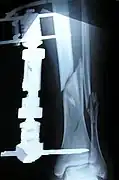

The photographs and radiographs illustrate the application and emplacement of an external fixator, an Ilizarov apparatus, to repair the open fracture of the lower left leg of a man. The photographs were taken four weeks after the patient fractured the shinbone (tibia) and the calfbone (fibula) of his left leg, and two weeks after the surgical emplacement of the Ilizarov apparatus to immobilise the leg and isolate the wound and fracture site to facilitate healing.

X-ray of the open fracture site immediately after installation of the Ilizarov apparatus.

X-ray of the fracture site and the emplaced apparatus, two months post-fracture; perspective 1-4.

X-ray of the fracture site and the emplaced apparatus, two months post-fracture; perspective 2-4.